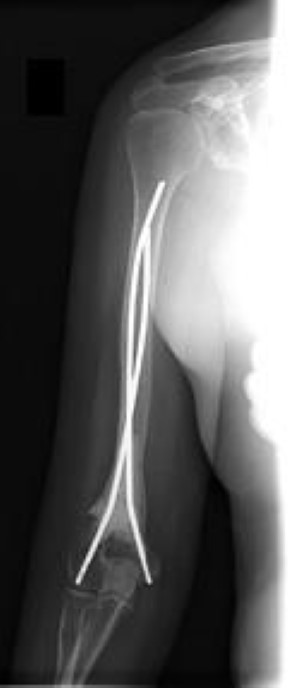

intramedullary rod in humerus

In this X-ray, the humerus has been stabilized with an intramedullary rod inserted down the center of the bone.

Reproduced from Schwartz HS, ed: Orthopaedic Knowledge Update: Musculoskeletal Tumors 2. Rosemont, IL, American Academy of Orthopaedic Surgeons, 2007, p 377.